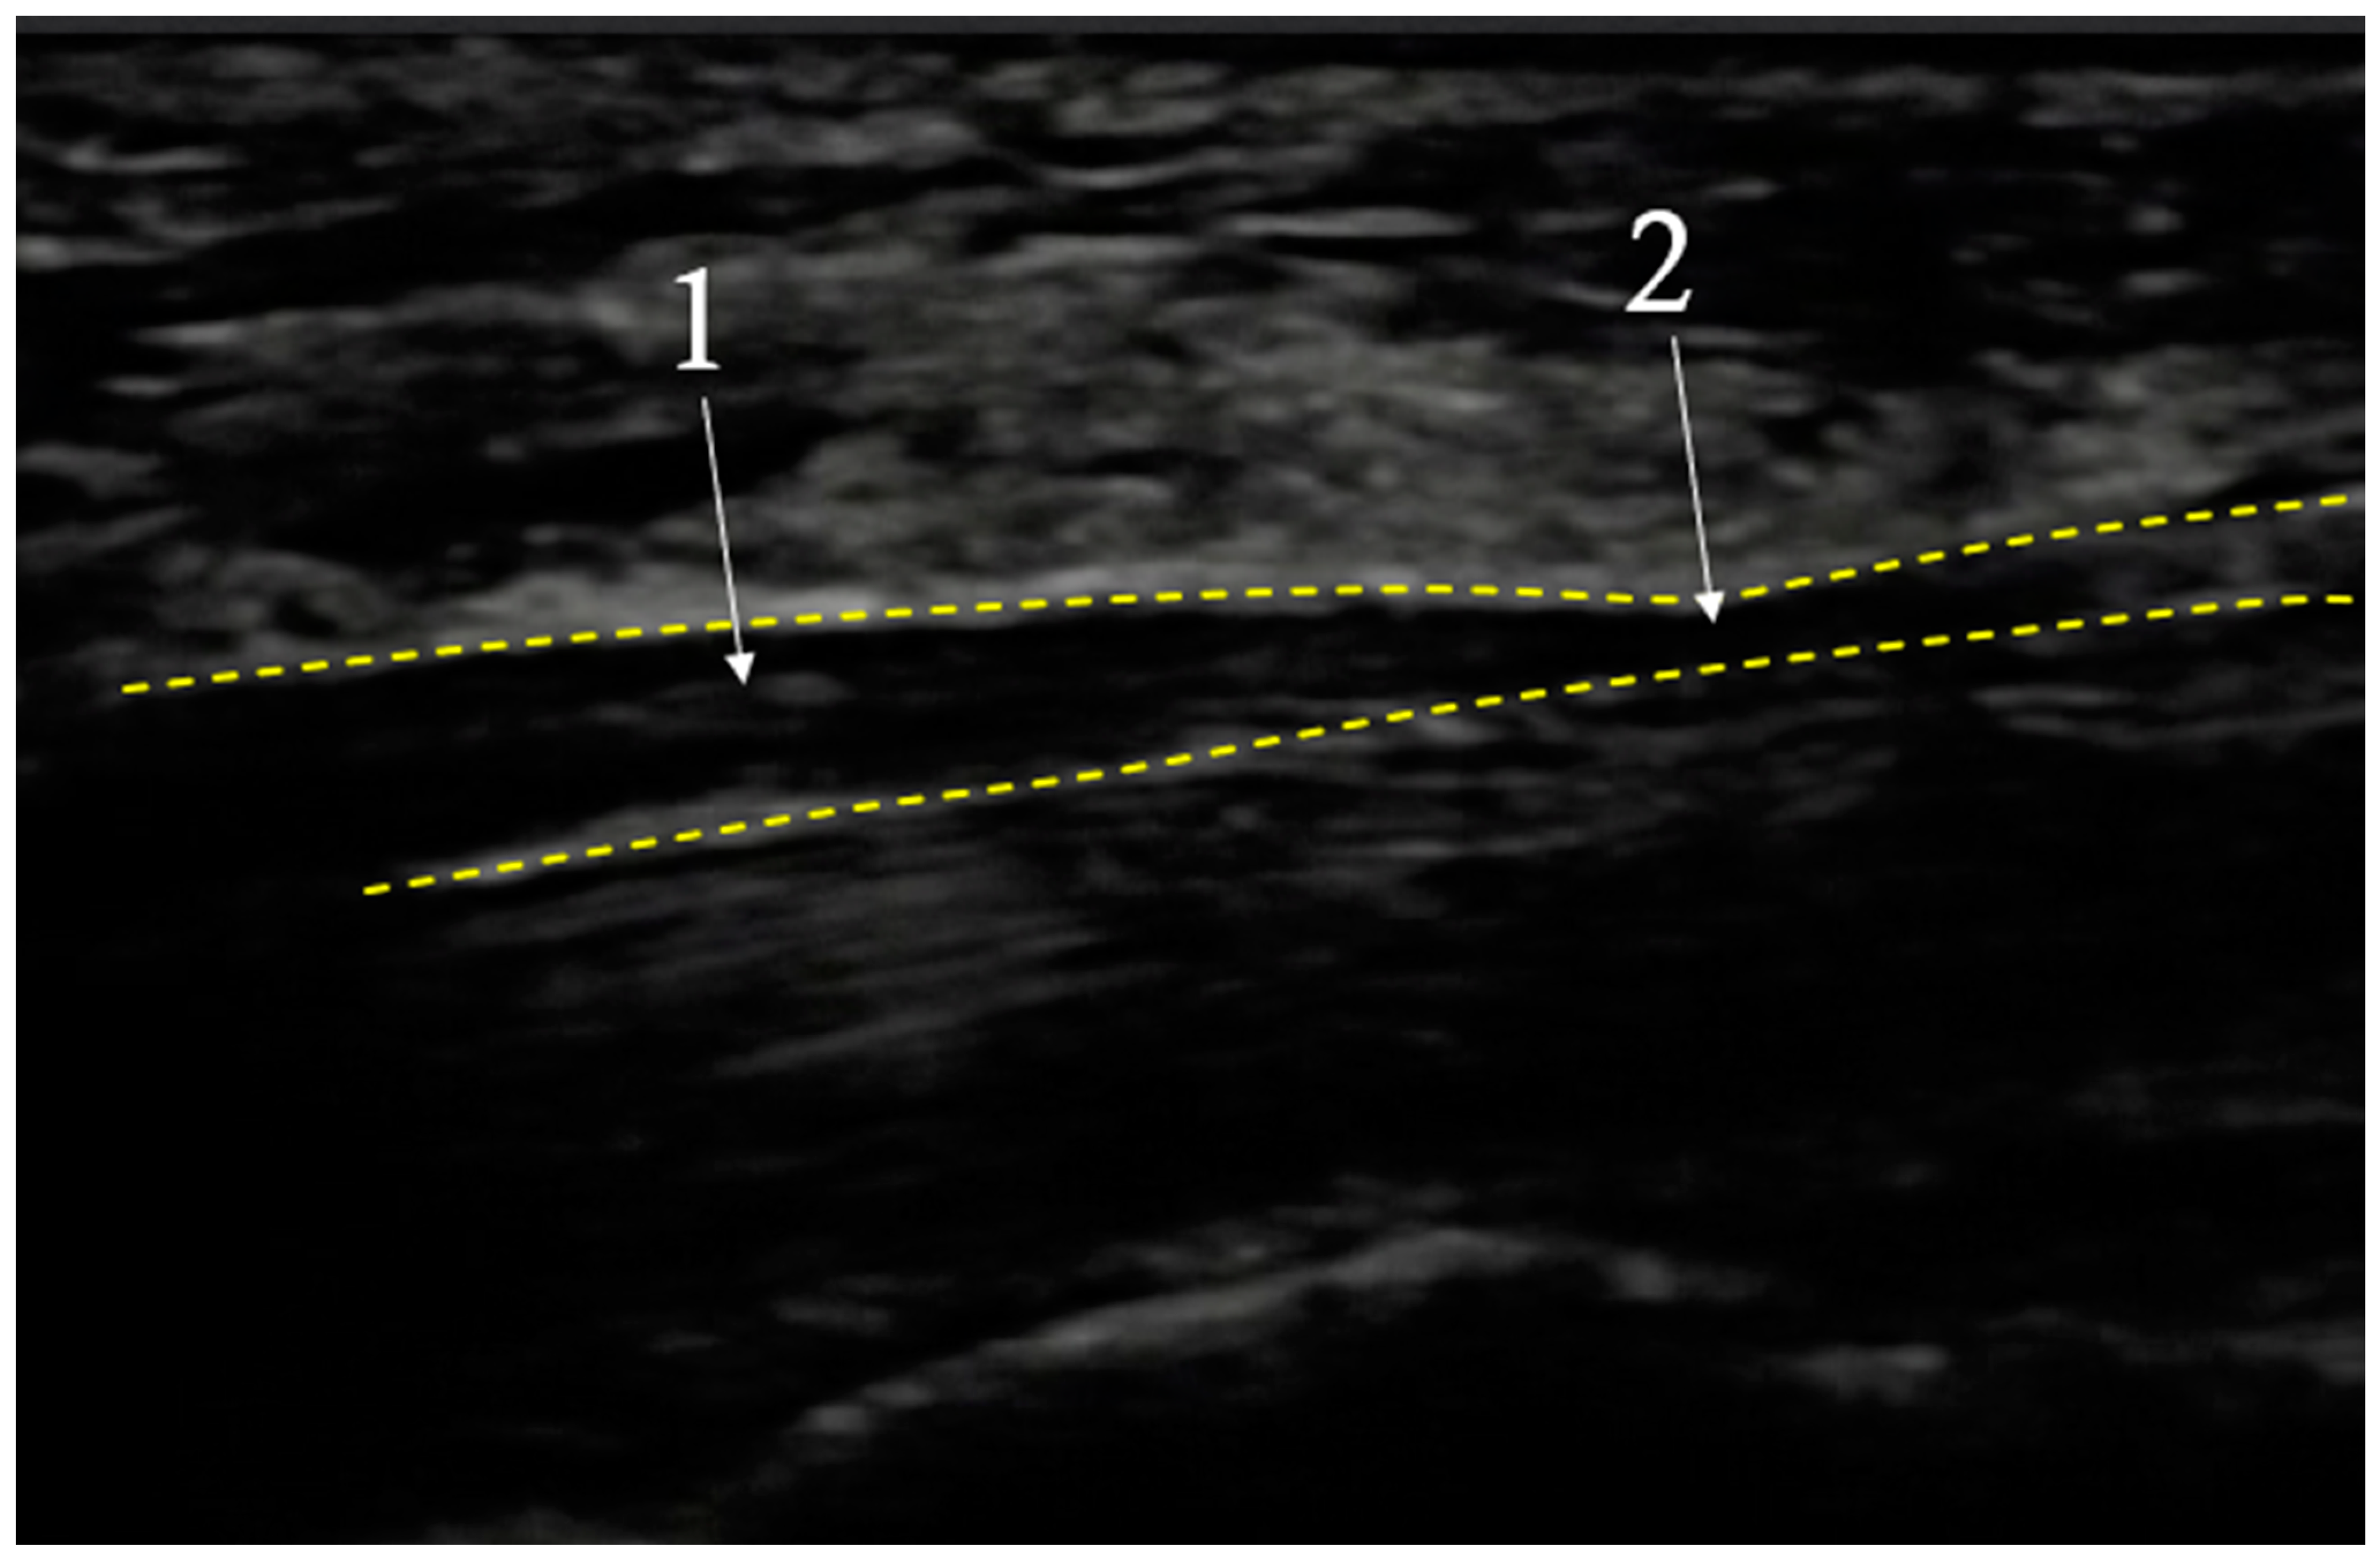

In cases where there are symptoms consistent with CTS together with normal physical and electroneuromyographic examination results, high resolution ultrasonography (USG) can be useful for diagnosis, showing thickening of medial nerve distally to the compression site [91,92] (Mov. 1). Buchberger et al. [93] were the first to diagnose this syndrome using USG and their findings have been confirmed in previous magnetic resonance studies [94,95]. The current criteria used for detecting CTS in magnetic resonance and ultrasonography are: edema of the MN at the entrance to the carpal tunnel and flattening of the MN, and arching of the flexor retinaculum at its exit from the carpal canal [96]. The overall sensitivity of ultrasonography for CTS is lower than that of physical examination and electromyography [81]. A typical image seen during USG examination of CTS is shown in Figure 1.

Figure 1.

Exemplary image seen during USG examination of Carpal Tunnel Syndrome. CTS—dotted line; Medial Nerve (MN)—contours; 1—nerve dilatation before carpal tunnel; 2—nerve compression in carpal tunnel; longitudinal cross section.